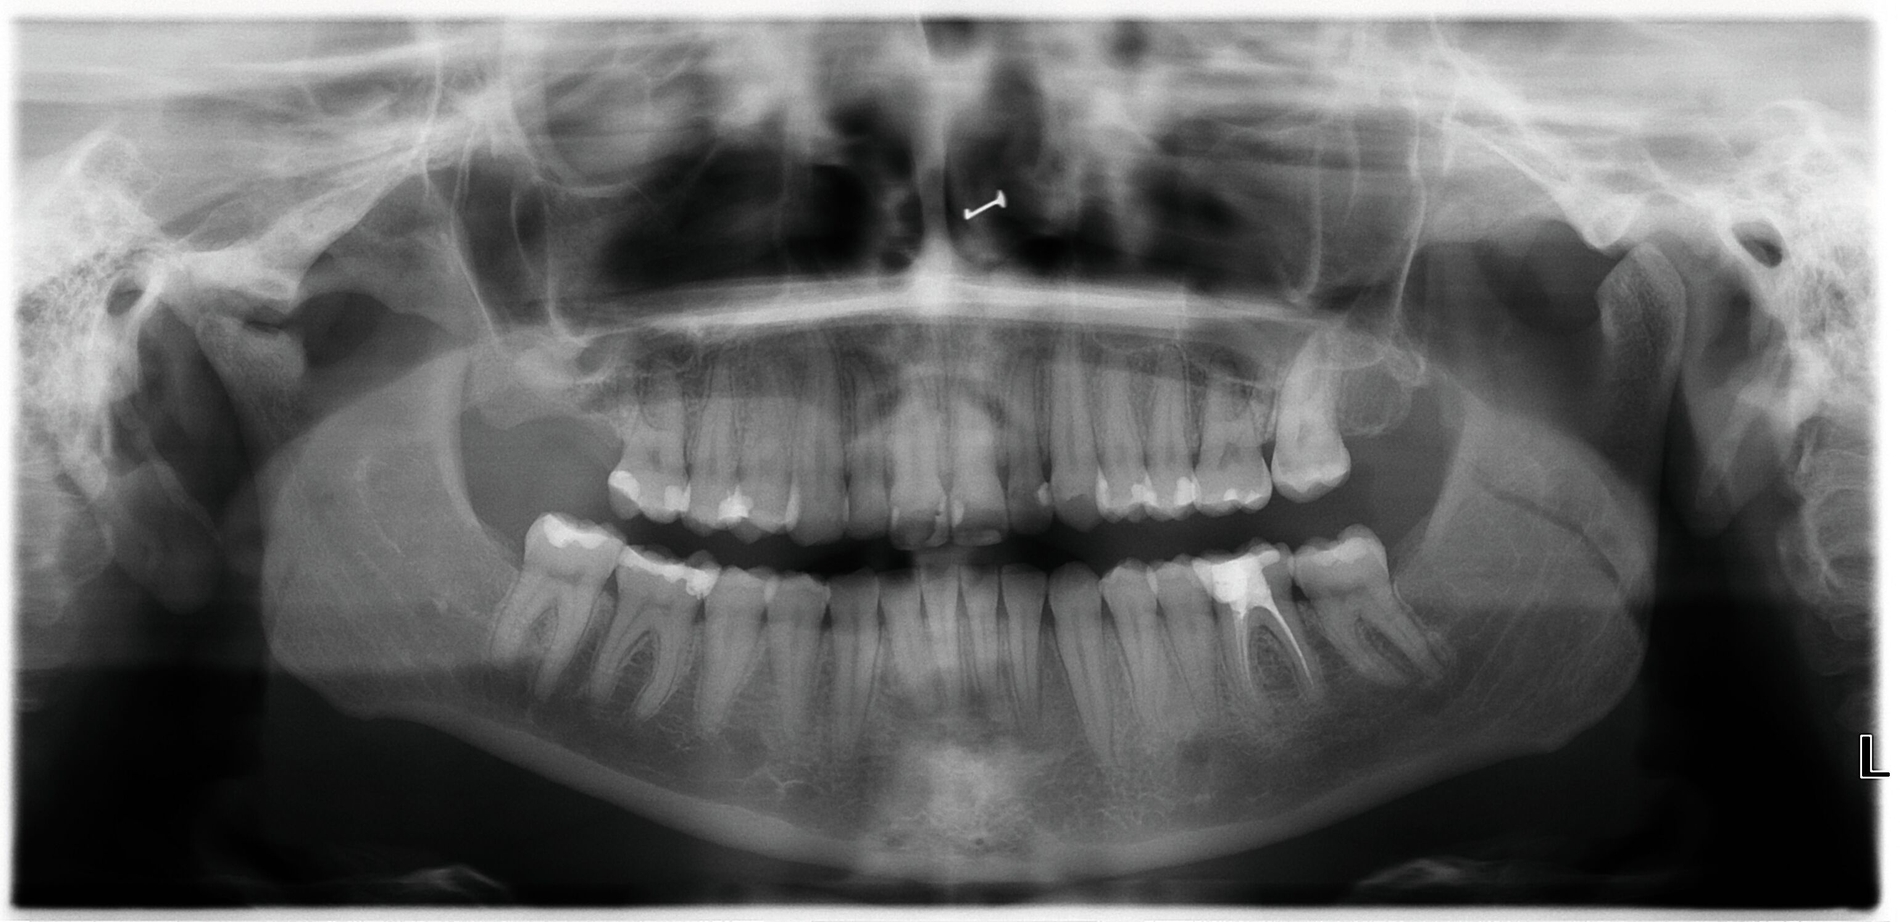

Die Achse-II-Diagnostik zeigte im Screening mit dem Fragebogen „Depression, Anxiety and Stress Scale“ (DASS) positive Befunde in den Dimensionen Depression, Angst und Stress. Es folgte die Durchführung einer aktuellen OPG-radiologischen Diagnostik. Diese zeigte Opazitäten im Sinne von Füllungen an diversen Zähnen und einer Wurzelfüllung 36; weiterhin eine deutlich abgeflachte und dysmorphe Struktur des Condylus articularis rechts sowie eine Abflachung des Condylus articularis links (Abbildung 3).

Weiterhin wurde eine MRT-Untersuchung veranlasst, die in der Befundung Zeichen der anterioren Diskusverlagerung mit Reposition links bei maximaler Kieferöffnung zeigte. Rechtsseitig zeigte sich das radiologische Vollbild einer Arthrose des rechten Kiefergelenks mit Degeneration des Discus articularis sowie geringgradiger Ergussbildung.

Die Diagnosen wurden unter Einbeziehung einer weiterführenden umfassenden Diagnostik in der Klinik für Rheumatologie in Bezug auf die systemische Diagnose der juvenilen idiopathischen Arthritis mit Beteiligung der Kiefergelenke, des Ellenbogengelenks sowie mit Verdacht auf Mitbeteiligung des Iliosakralgelenks spezifiziert.